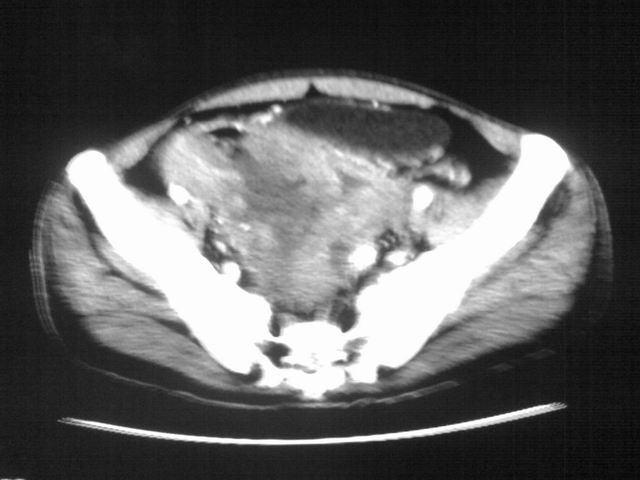

患者m 56岁,盆腔及下腹部胀痛半年,加重1月余,消瘦\中重度贫血.(附:平扫时直肠的高信号为,残留的钡剂).补一下病史:胃镜及纤维结肠镜均无明显异常.

首先是病灶的定位,平扫看很象肠管肿瘤但既然纤维结肠镜正常就可以除外结肠病变,增强成不均匀强化,位于右下腹部应该首先考虑回肠末段占位性病变,1淋巴瘤,2间质瘤,3腹膜后神经原肿瘤待除外,

膀胱后方及直肠前方见巨大混杂密度影,与前列腺相连且向膀胱内突入,精囊腺显示不清;考虑前列腺癌侵犯精囊、膀胱。

膀胱及直肠间有不规侧的软组织密度影,内密度不均匀。其内有坏死囊变,前列腺及精囊腺,膀胱后壁受浸。结合病史考虑腹膜后肉瘤可能性大。